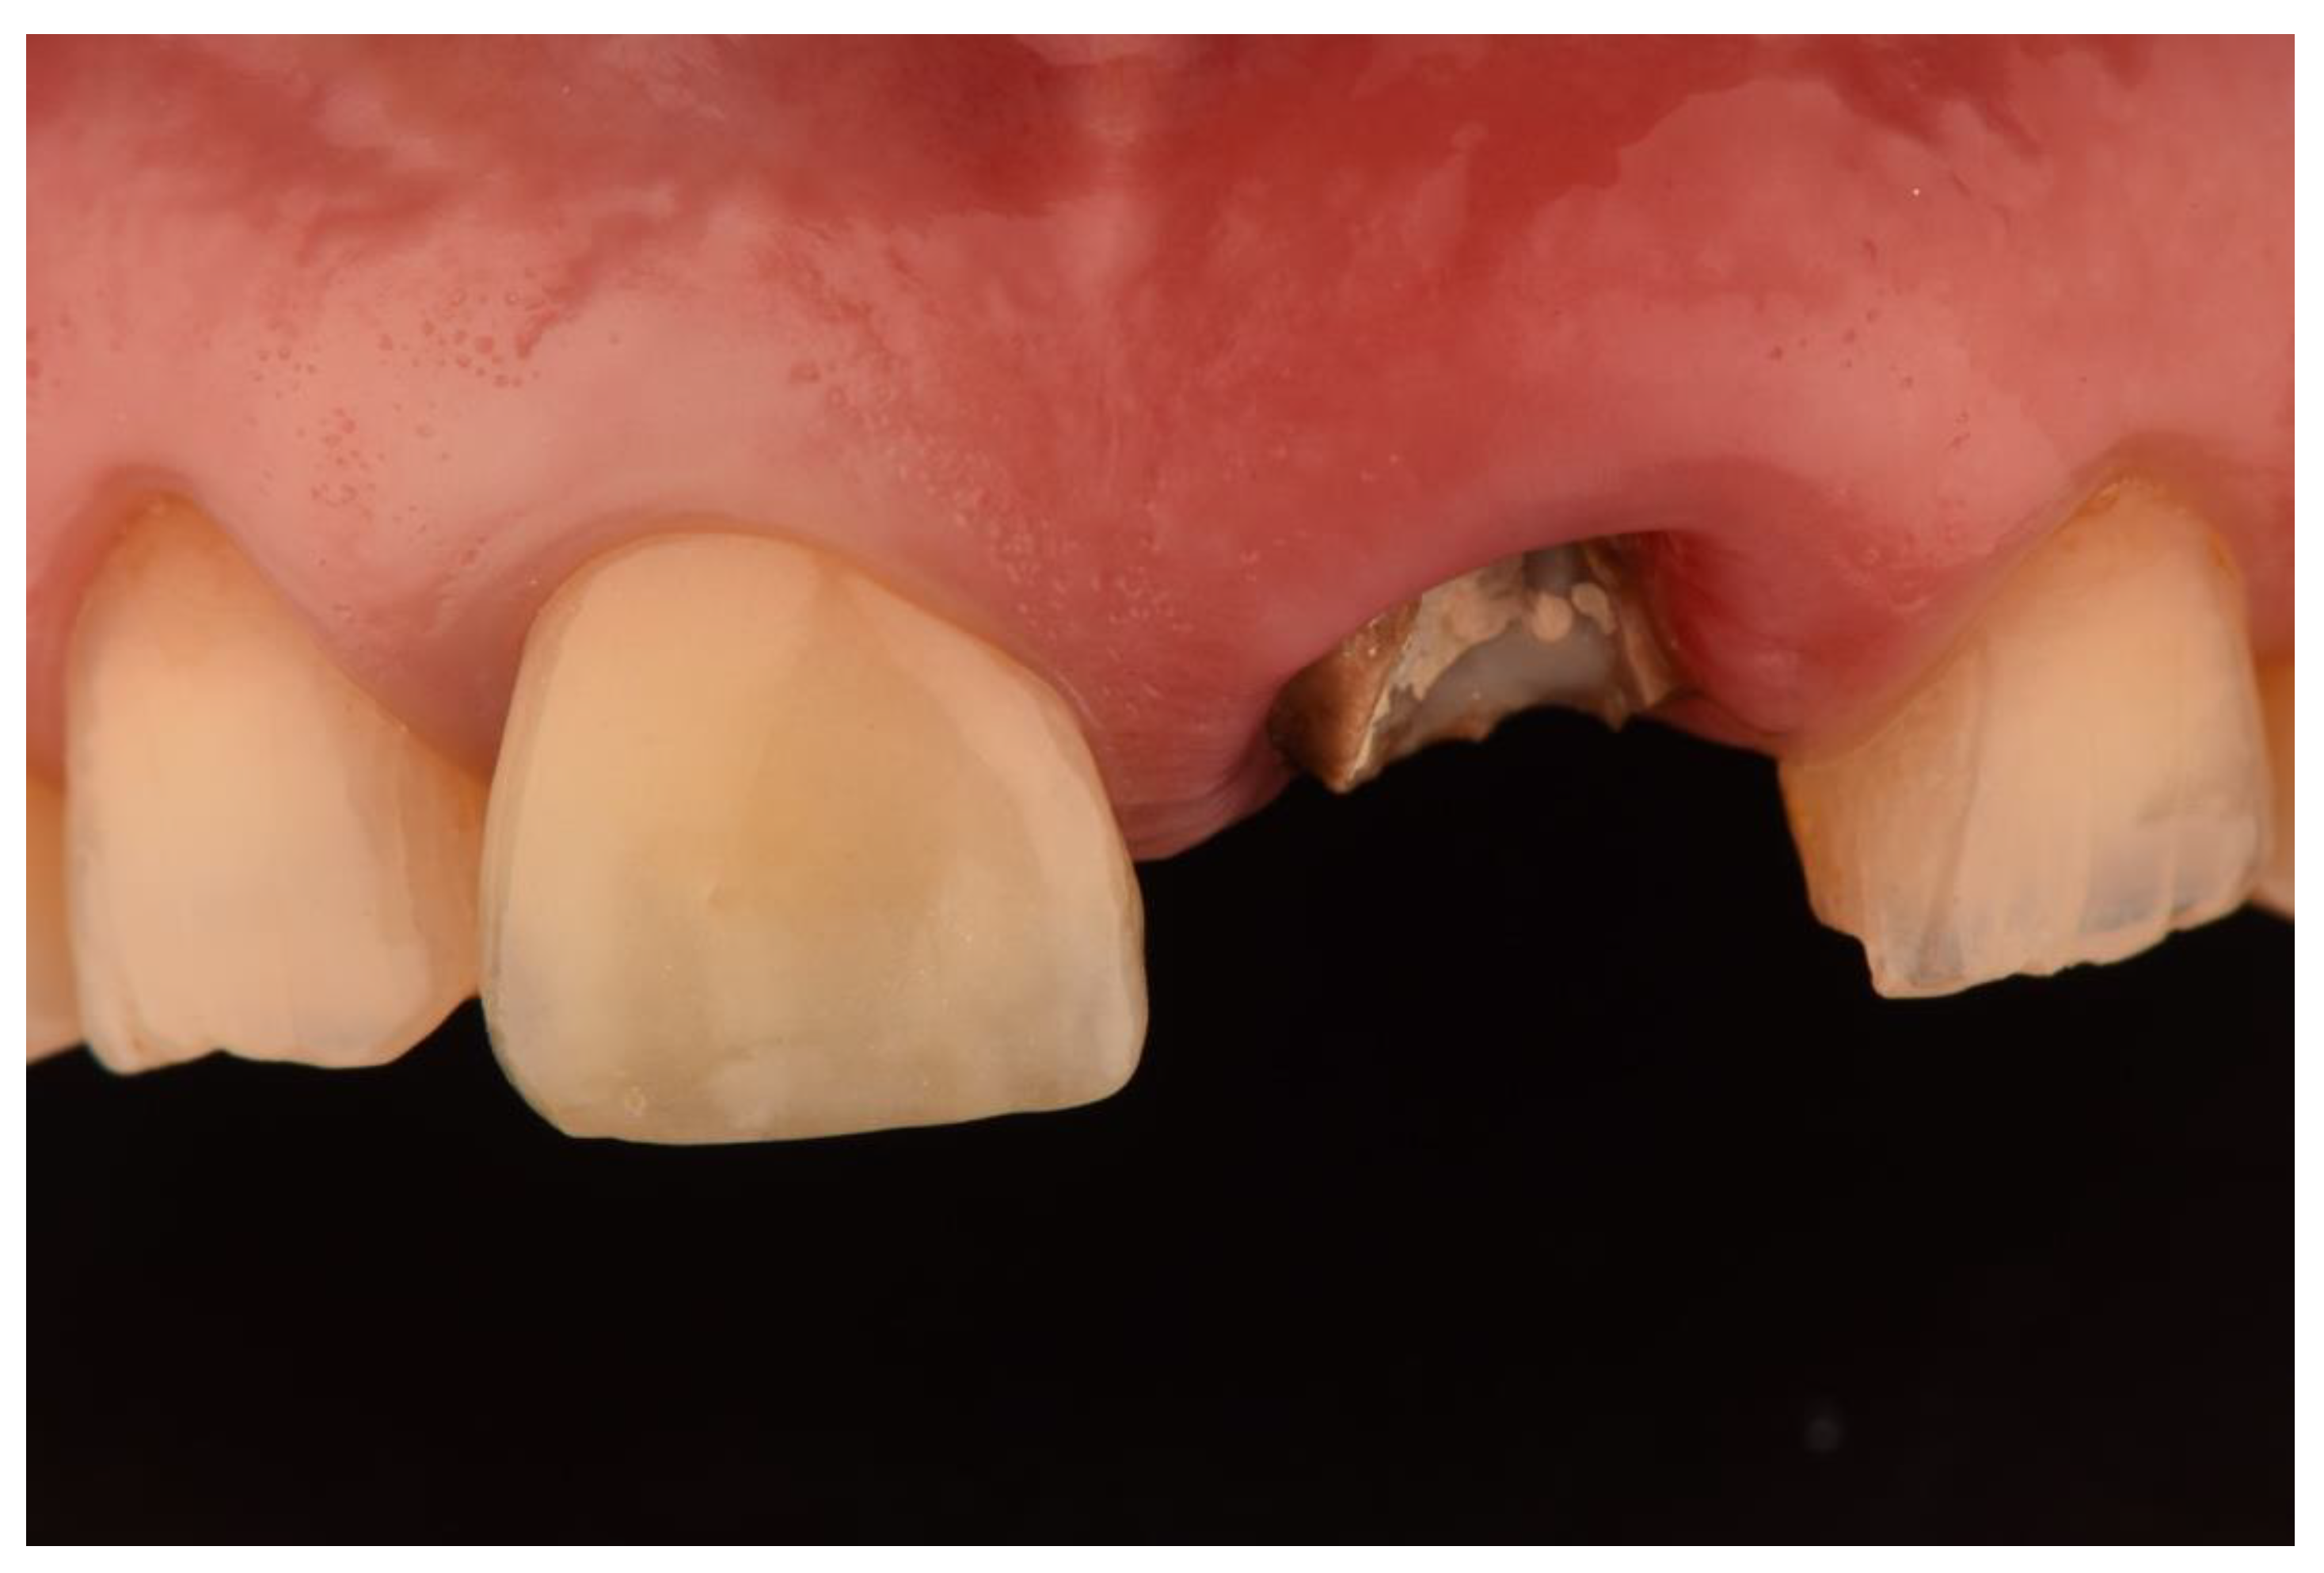

2. Materials and Methods

3. Results